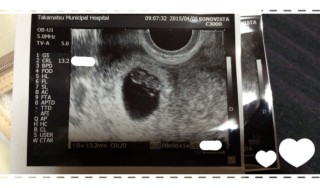

写真:7w5d:桃さん

胎芽13.4mm!

無事に胎芽・心拍を確認できました!

前回の5w5dでは胎嚢と卵黄嚢のみでしたが、2週間でしっかりと赤ちゃんが見えて感動しました!